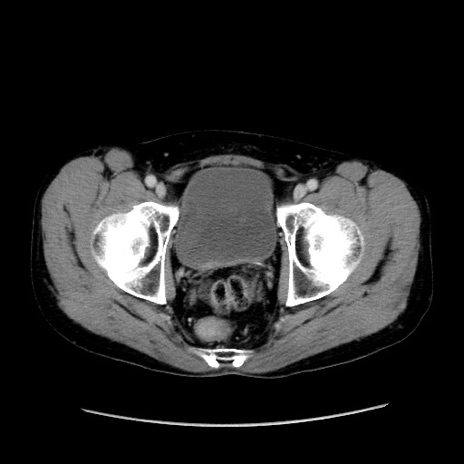

症例37(横断像)

【症例】40歳代 男性

【主訴】腹痛

【現病歴】4時間ほど前に電車に乗車中に臍部上より腹痛出現。徐々に増悪し起立困難となり、救急外来受診。生ものは数日食べていない。今朝お雑煮を食べた。

【身体所見】BT 36.8℃、BP 117/84mmHg、HR 91/min、SpO2 97%、苦悶様、腹部:臍上部広範囲圧痛あり、反跳痛±

【データ】WBC 8100、CRP 0.03